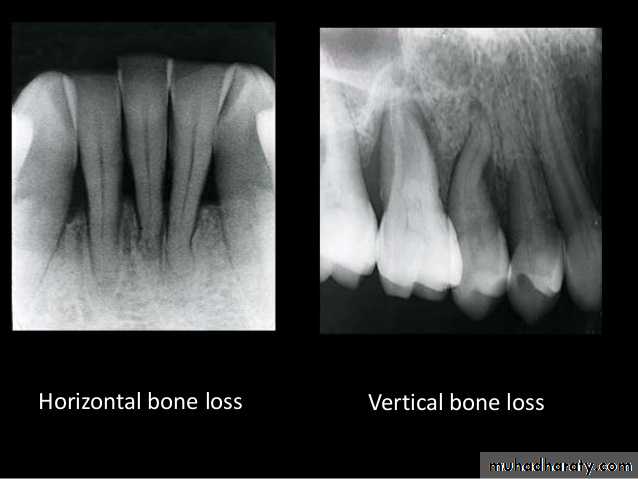

Intercrestal bone should be parallel with line dawn from the CEJ of one tooth to that of the contacting tooth.

1. Horizontal bone loss:- When loss occurs on a plane that is parallel with a line drown.

2.Vertical bone loss:- when there is greater bone loss in one tooth than on the adjacent tooth, so the bone level is not parallel with a line joining the CEJ.